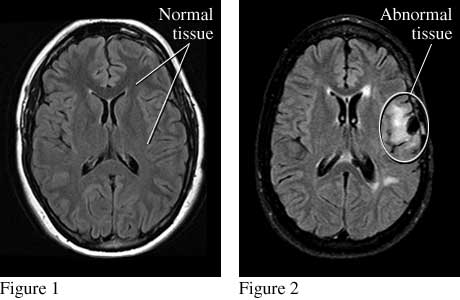

Seizure MRICourtesy of Intermountain Medical Imaging, Boise,

Idaho. All rights reserved. Top views of the brain show normal tissue (see figure 1) and

abnormal tissue (from an injury) that causes seizures (see figure 2). ByHealthwise Staff Primary Medical ReviewerJohn Pope, MD - Pediatrics Specialist Medical ReviewerSteven C. Schachter, MD - Neurology Current as ofOctober 14, 2016 Current as of: